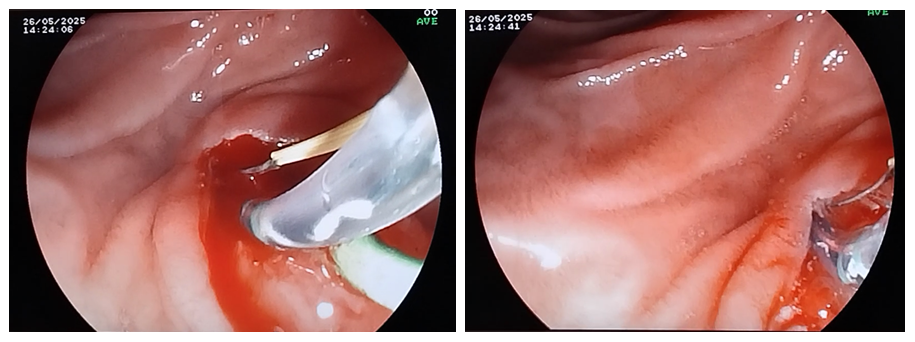

In the postoperative period, transient hyperamylasemia, with a rise no more than three times above normal, without clinical signs of pancreatitis, was observed at approximately the same rate in each group, averaging 13-18% of cases. To determine the severity of acute pancreatitis, we followed the classification adopted at the 1992 Atlanta expert meeting.The clinical picture of mild acute postoperative pancreatitis (APP), with complete relief by conservative treatment, was more often observed in the third group - 7.9%, in the first group - 4.4%, in the second group - 2.5%.Severe acute postoperative pancreatitis (APP) developed in 4 patients (1.8%) in the first group, in 2 patients (7%) in the second group, and in 2 patients (20%) in the third group, which required long-term treatment of the patient in the intensive care unit or additional surgical interventions.In cases of acute postoperative pancreatitis, conservative treatment was used in most cases, along with minimally invasive procedures if complications arose. Patients lost their lives in four patients in the first group and one woman in the third group. The overall mortality rate was 0.2% across the three groups. Since 2022, if acute pancreatitis is diagnosed in the early preoperative period, we have been using endoscopic stenting of the pancreatic duct to restore normal pancreatic fluid outflow. Pancreatic stents with a diameter of 5 Fr and a length of 5-7 cm were used for prosthetic placement. Pigtail stents were preferred to prevent migration from the internal ducts. In the early preoperative period, stenting of the pancreatic duct was successfully performed in 14 (87.5%) of 16 attempts. In each case of successful stenting, the clinical picture of acute pancreatitis was predicted, but one patient died due to multiple organ failure. After the symptoms of acute pancreatitis subsided, the stent was removed within 5-14 days.It should be noted that in some cases, the stent may spontaneously migrate into the intestine, but endoscopic monitoring requires fluoroscopy to detect migration from the internal duct. We believe that prophylactic APP stenting is necessary to stop endoscopic bleeding, as any mechanical or thermal hemostasis methods can create a blockage over the pancreatic duct and cause acute pancreatitis (Fig. 3). In our practice, we also observed the development of clinically significant acute pancreatitis with ongoing bleeding from the EPST zone of the pancreatic duct in four clinical cases, and we identified the formation of dense blood clots in the ampulla area. These patients successfully eliminated the symptoms of pancreatitis and bleeding through delayed endoscopic hemostasis and APJ stenting. | Figure 3. Prophylactic stenting of the APP, performing thermocoagulation to stop bleeding from the papillotomy incision |